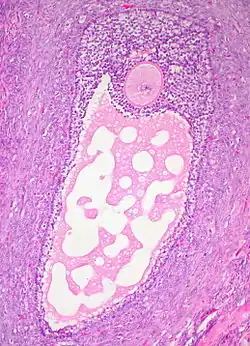

![]() | |

| Cystadenoma | Serous cystadenoma | Cyst lining consisting of a simple epithelium, whose cells may be either:[21]

|

![]() |